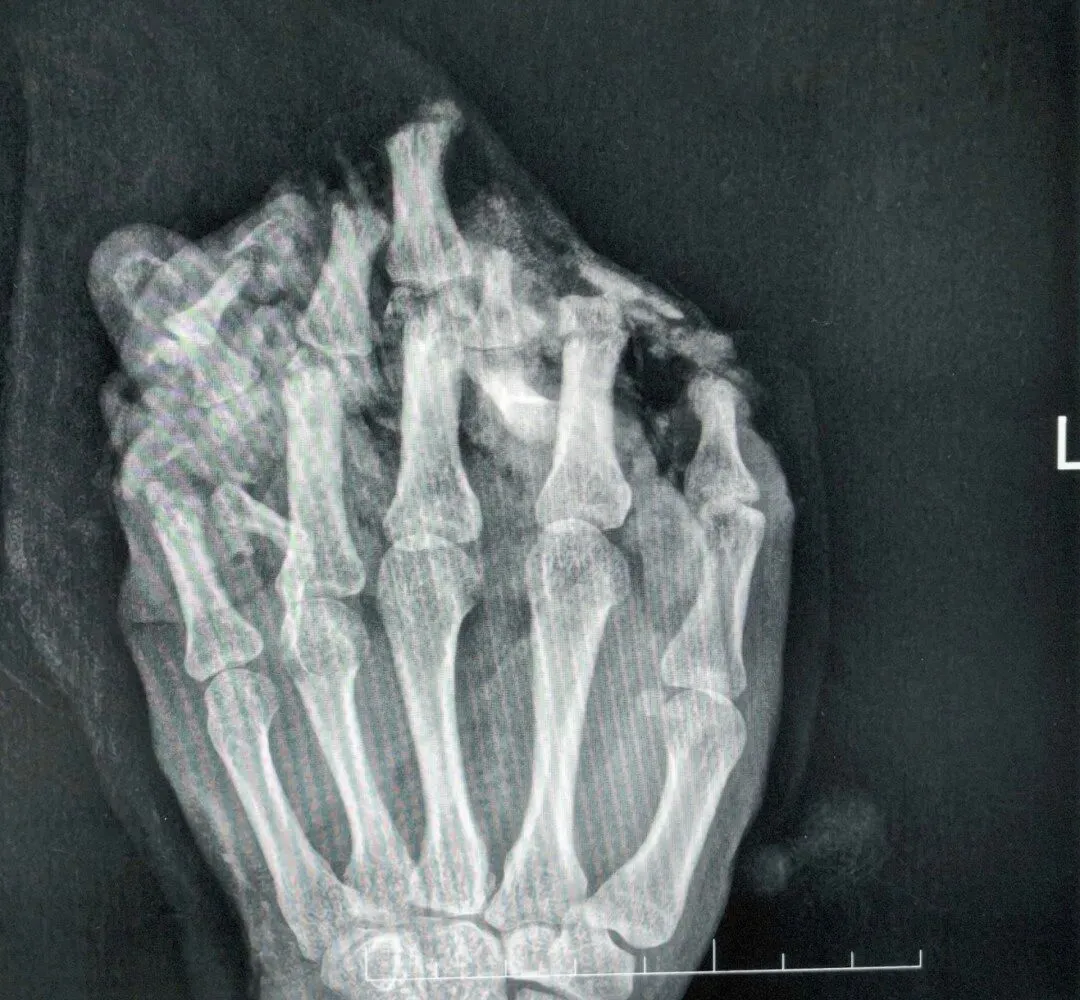

医生诊断他为:1.左手掌、手背,示指中指环指小指掌侧及背侧皮肤毁损脱套伤;2.左手掌、手背及各指肌腱神经血管损伤;3.左手多发性开放性指骨骨折伴毁损;4.左拇指末节指腹皮肤、软组织缺损;5.左拇指固有神经断裂;6.左拇指甲床裂伤。

医院随即为小王做了手术,术中,医生们完成了彻底的清创,修复了骨折、断裂的肌腱与神经。

为覆盖巨大创面,医生启用了经典的“腹部带蒂皮瓣”,将断手“寄养”在了带有自身血供的腹部皮肤上,为后续所有修复提供了生存的土壤。

经过近一个月的“腹手相连”,皮瓣在手部建立了新的血运。医生们进行了“断蒂”手术,让手从腹部独立,患者也获得了活动自由,为功能锻炼打下基础。